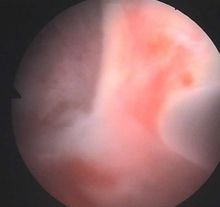

宫腔粘连b超图片最新

宫腔粘连b超图片最新,宫腔粘连b超图片

宫腔粘连

宫腔粘连图片宫腔镜

宫腔粘连图片

宫腔粘连高清图片

轻度宫腔粘连图片

重度宫腔粘连图片

宫腔粘连宫腔镜